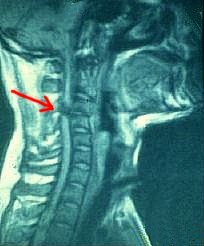

Les lesions de medul·la espinal poden causar trastorns motors del sistema nerviós, presentant contraccions musculars. Aquests síntomes constitueixen l'espasticitat i provoquen alteracions del moviment i...